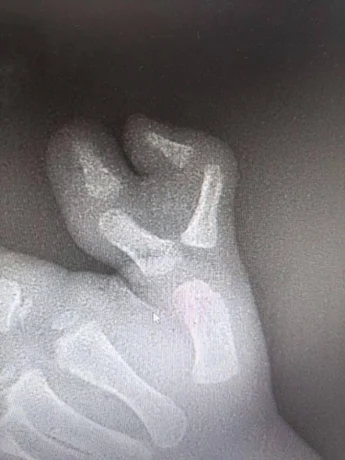

- У маленького пациента рос добавочный палец, вызывая как физические, так и психологические трудности. После всех необходимых диагностических мероприятий ребенку провели операцию, - сказано в сообщении.

Как уточнили в пресс-службе, операция прошла успешно. На данный момент ребенка уже выписали из стационара на амбулаторное лечение по месту жительства. После полного восстановления мальчика ждет повторная операция для удаления металлоконструкции. Однако в дальнейшем функция кисти полностью восстановится, передает сайт Минздрава.

Подмосковные врачи удалили ребенку шестой палец на руке / Фото: Пресс-служба министерства здравоохранения Московской области